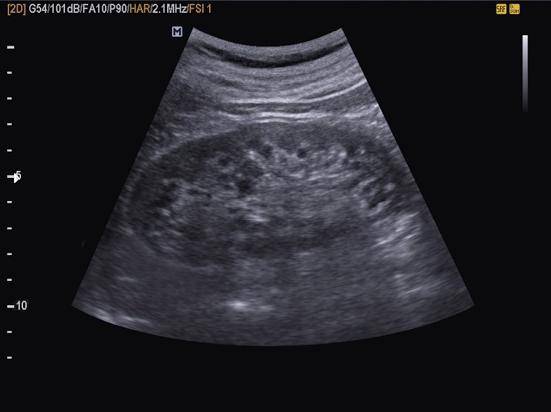

УЗИ печени следует делать строго на голодный желудок, а перед самим обследованием нельзя пить даже воду. Данное исследование проводится в нескольких проекциях, лежа на спине, на правом (и/или левом) боку, стоя и сидя. Диагностика при помощи ультразвукового обследования дает возможность обнаружить любые новообразования в печени, желчном пузыре, определить присутствие паразитов, цирроз, метастазы, наличие травмы, абсцесс, диагностировать синдром Бадд-Киари (возникновение закупорки венозного оттока), гипертензию, проверить кровеносные сосуды и протоки, а также измерить доли печени.

Если печень здорова и ничем не поражена, то ее правая доля составляет до 12,5 см, левая — 7 см, проток в пределах 8 мм, портальная вена — до 13 см, ее края ровные, а структура однородная.